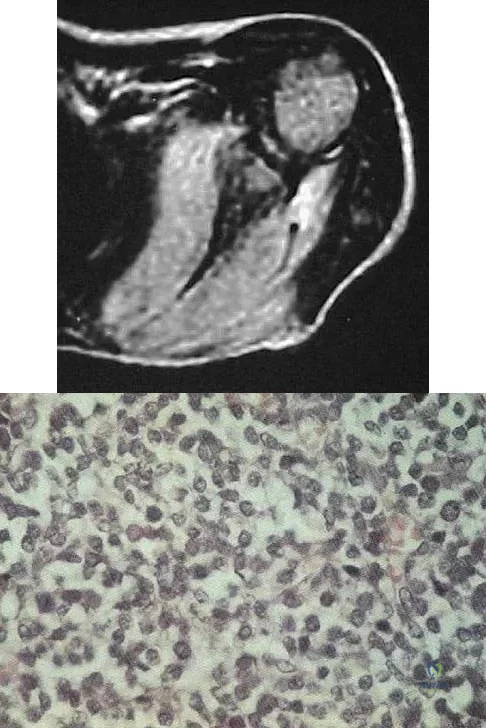

A 28-year-old man reports knee stiffness, swelling, and a constant ache that is worse with activity. Examination reveals an effusion, global tenderness, and warmth to the touch. Flexion is limited to 110 degrees. Figures 48a through 48d show sagittal T1-weighted, sagittal T2-weighted, axial T1-weighted fat-saturated gadolinium, and axial gradient echo MRI scans. Based on these findings, what is the most likely diagnosis?

Explanation

The MRI scans show multiple low-signal intensity lesions scattered throughout the knee, extending posteriorly inferior to the tibial plateau. The low-signal intensity on both the T1- and T2-weighted images, the modest vascularity noted on the gadolinium image, and the "blooming" noted on the gradient echo image (ferrous-laden tissue) are all strongly suggestive of diffuse PVNS. Whereas synovial chondromatosis can present as diffuse masses in the knee, they present as nodule masses that have low T1- and high T2-weighted signal characteristics. Resnick D (ed): Diagnosis of Bone and Joint Disorders. Philadelphia, PA, WB Saunders, 2002, pp 4241-4252.